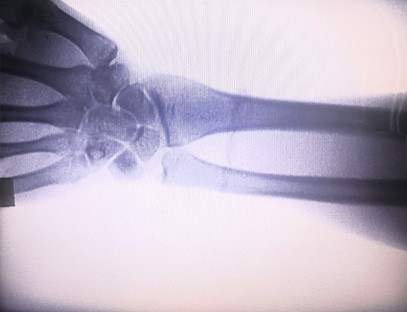

Una màquina de raigs X portàtilés un instrument portàtil de baixa dosi de radiació i molt segur que pot obtenir imatges d'alta qualitat alhora que redueix l'exposició a la radiació. Compensa les deficiències dels grans equips hospitalaris i es pot moure i transportar en qualsevol moment. Especialment indicat per a unitats i particulars amb pressupost insuficient i requeriments baixos d'imatges. La nostra màquina de raigs X de nova generació està equipada amb una pantalla gran d'alta definició de 10 polzades, que té un rang d'angle de visió més gran i pot veure completament a través de tota la palma, incloses fractures, luxacions, artritis i tumors ossis. Es pot connectar a una impressora de pel·lícules per imprimir pel·lícules ortopèdiques i també es pot utilitzar per a la producció i proves industrials. No cal una cambra fosca, perspectiva directa, observació en temps real. Aquesta màquina té un sistema d'imatge d'alta resolució que pot capturar imatges de qualsevol estructura òssia de manera molt clara. Proporcionar els millors equips i solucions de proves de raigs X per a fabricants de productes mèdics, mascotes, industrials, electrònics, departaments d'inspecció i manteniment i laboratoris d'investigació.

Especialització:Dissenyat per a les necessitats de les clíniques ortopèdiques, especialment indicat perImatge de raigs Xd'extremitats com mans, canells, colzes, espatlles, genolls, turmells, etc.

Imatge clara:La tecnologia d'imatge digital avançada s'utilitza per proporcionar imatges de raigs X d'alta qualitat, ajudant els metges a diagnosticar la malaltia amb precisió.